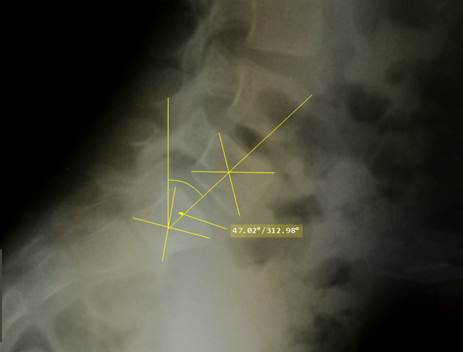

Для

измерения выявленных изменений проводится расчерчивание бокового снимка по

Митбрейту. Определяют центры тел пятого поясничного и первого крестцового

позвонков на боковой рентгенограмме. Для этого провоядт линии из взаимо

противоположных углов тела каждого позвонка, место их пересечения и будет

центром. Между центрами тел проводят линию, которую пересекают вертикалью, взятой от края снимка. Угол между ними

называется уголом Митбрейта.

Угол

Митбрейта отражает наклон крестца. В норме он равен менее 30°. Если угол больше

30°, то такой крестец считается чрезмерно наклонённым, или острым. Он может

обнаруживаться как в изолированном виде, так и в составе деформаций

позвоночника: плоской спины и плоско – вогнутой спины. При значениях угла Митбрейта больше 45° высок риск развития спондилолиза и спондилолистеза.

Снимок

поясничного и крестцового отделов позвоночника девочки 8 лет с нарушением

осанки по типу поско – вогнутой спины. Расчерчивание по Митбрейту. Определяется

увеличение наклона крестца до опасных в плане развития спондилолистеза

значений.

выполненные в стационаре: угол Митбрейта на боковой рентгенограмме составил

42°, иной патологии не обнаружено. Диагноз: Перенапряжение в пояснично –

крестцовом соединении с болевым синдромом. Картина острого крестца. Подозрение

На боковом снимке поясничного и крестцового отделов позвоночника отчетливо

виден спондилолистез: задние края 5 поясничного и 1 крестцового позвонков

обозначены стрелками, видно смещение 5 поясничного позвонка вперед в пределах 1

четверти ширины тела первого крестцового

позвонка (1 степень по Меердингу). Угол Митбрейта 53° - значительно увеличен. На аксиальном скане 5